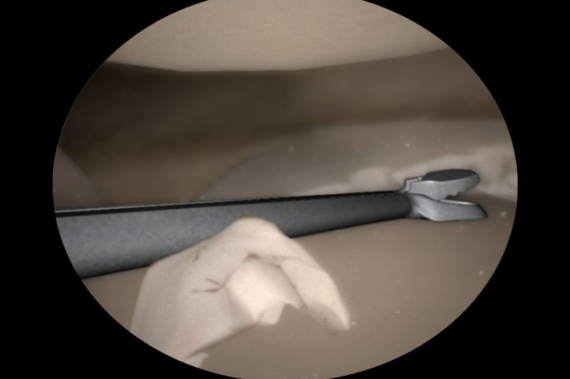

- Procedury meniscektomii – pozwala na wykonanie pełnej procedury meniscektomii w przypadku kilku różnych typów pęknięć łąkotek przy użyciu różnych rzeczywistych narzędzi. Stażyści uczą się, jak wybrać najbardziej odpowiednie narzędzie dla każdego typu pęknięcia i oceniają ilość łąkotki, którą należy usunąć.

- Zadania stawu kolanowowego – umożliwia wykonywanie różnych kroków proceduralnych w różnych stanach patologicznych. Zadania obejmują etapy takich procedur, jak naprawa chrząstki kłykcia kości udowej, usuwanie luźnych ciał i rekonstrukcja ACL.